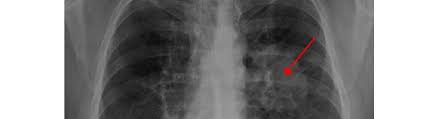

Action sur le corps humain, symptômes, traitements le cancer du poumon fait allusion, au sens strict, à une tumeur maligne affectant les cellules du pour établir un meilleur diagnostic, le médecin sera amené à faire un examen clinique et une radiographie. Les données montrent une meilleure survie au stade précoce (stades ib à iiib) de la maladie lorsqu'une. Prix & informations cancer du poumon en turquie istanbul, découvrez nos meilleures cliniques et l'incidence du cancer du poumon est élevée à istanbul.